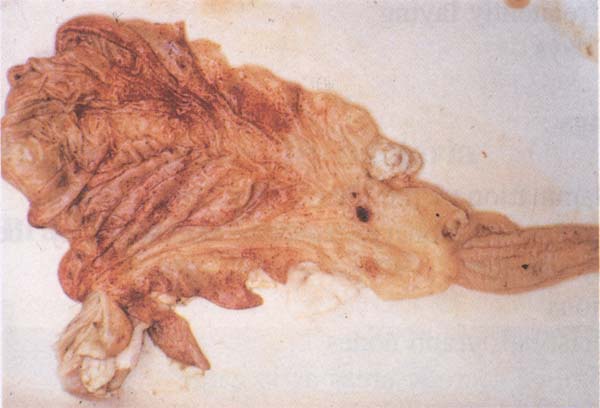

- Midelerin (Şekil 161) ve bağırsakların akut hemorajik iltihabı

Karar : Ateş ve akut gastrointestinal lezyonlarla birlikte görülen akut hastalıktan etkilenen bir hayvanın karkası kınanır . İyileşen hayvanların ve sistemik olmayan veya yaygın lezyonları olan hayvanların karkası onaylanır . Etkilenen organlar kınanır .

Şekil 161 : Nairobi koyun hastalığı. Midelerin akut hemorajik iltihabı.